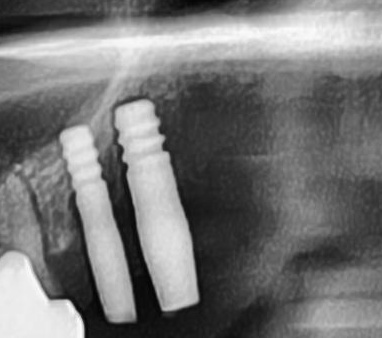

しっかりとインプラント埋め込まれた後は、動揺がないか、噛んだ時に当たらないかなどを確認して、最後にパノラマ写真を撮影して今回のオペは終了となりました。